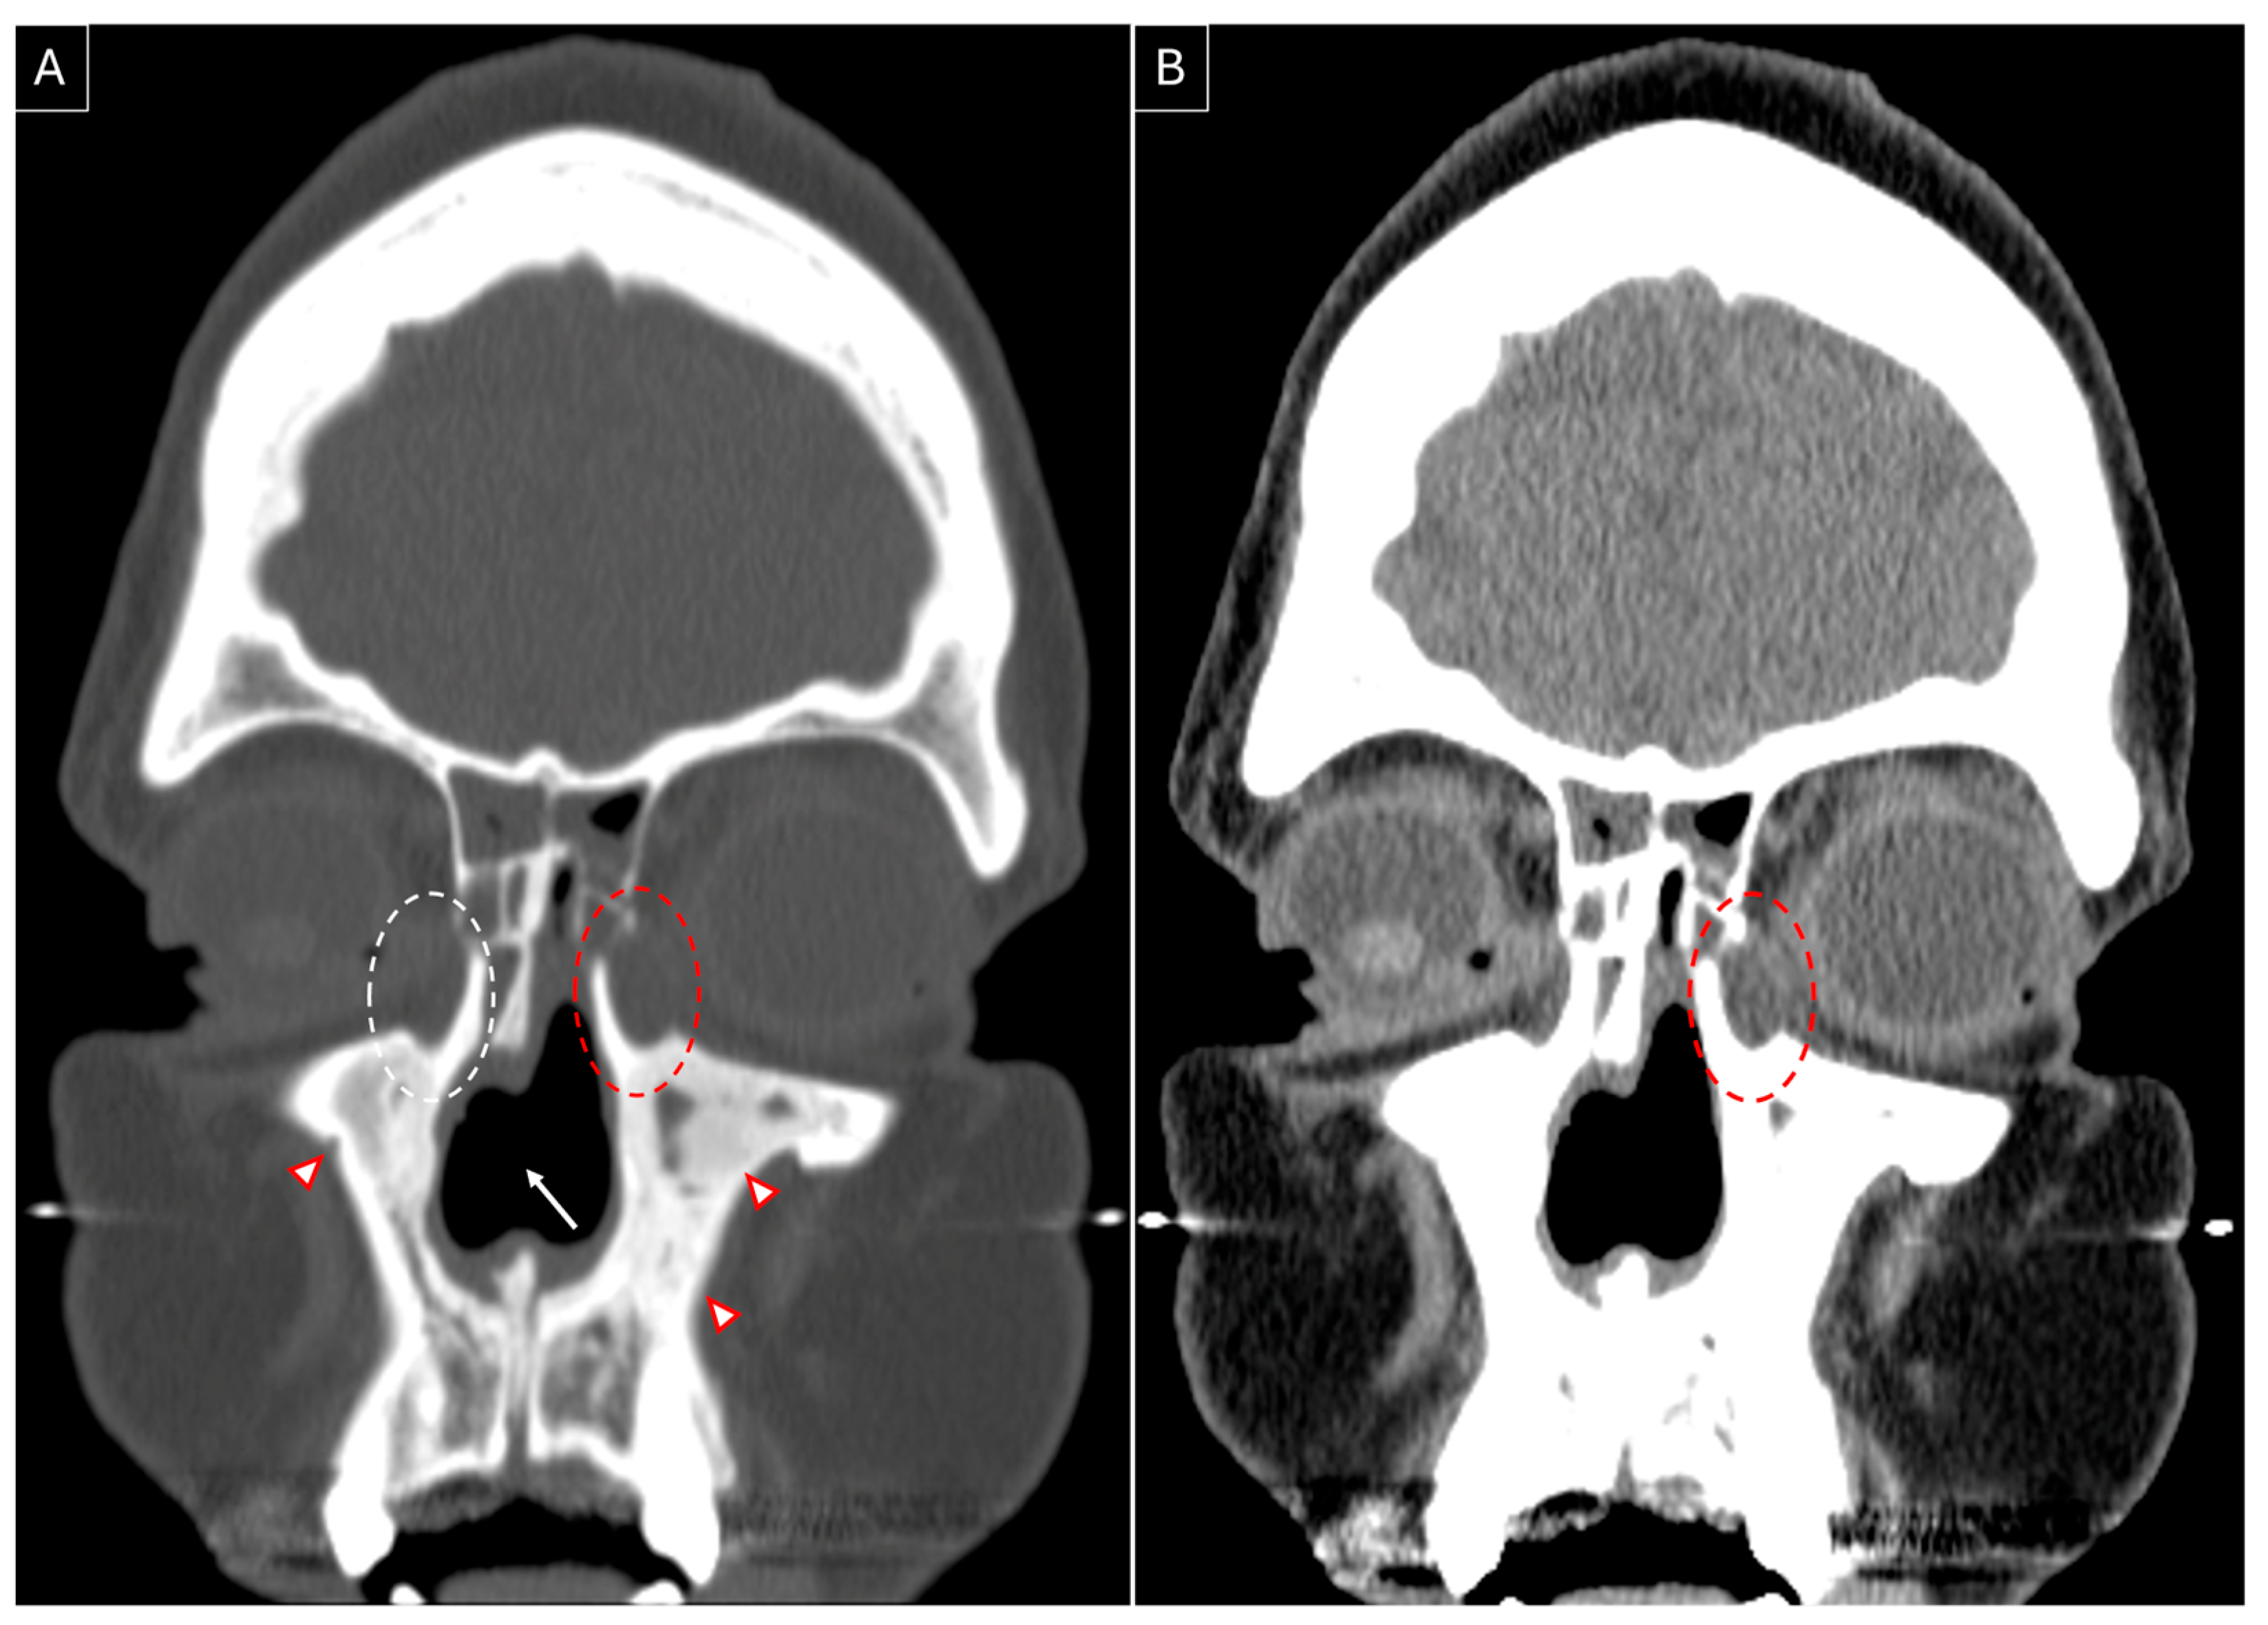

3.3. Our Experience: Two Patients of GPA Who Underwent Endoscopic DCR